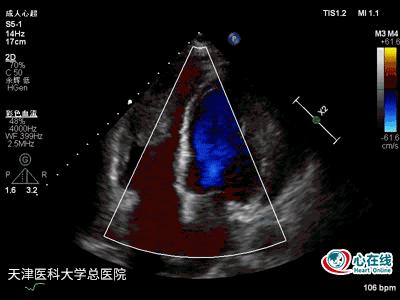

图4. 彩色多普勒心尖四腔心切面示二尖瓣、三尖瓣可见少量反流信号。